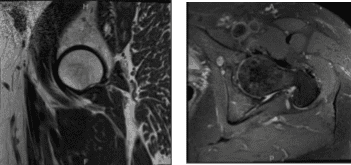

Visitó después de una semana para una revisión y presentó los resultados de su resonancia, mostrando un leve cambio degenerativo en la cadera izquierda con inserción del glúteo tendinoso medio y desgarros parciales con bursitis mayor leve. Cambio degenerativo leve en la cadera DERECHA. Tendinosis del glúteo mínimo insertional y desgarro parcial con bursitis trocantérica mayor leve.

Resonancia magnética 3T sin contraste en la cadera izquierda

MRI-3T cadera derecha sin contraste